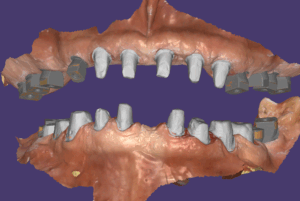

모든 임플란트는 골융합이 잘 되었고 스캔바디를 끼우고 스캔을 한 다음 디자인해서 치아를 만들었습니다. 저희 병원은 치기공 100% 모두 자체적으로 가공을 하고 있어요. 모든 장비를 다 갖추고 있구요. 기공을 제가 직접 하게 된 스토리는 길어서 다른 글에서 보시면 될 거 같아요. 아무래도 제가 임상에서 깨달은 부분을 디자인에 직접 적용하기 위함이 큽니다.

스캔바디를 끼운 모습이구요.

지대주 디자인이 된 모습이에요.